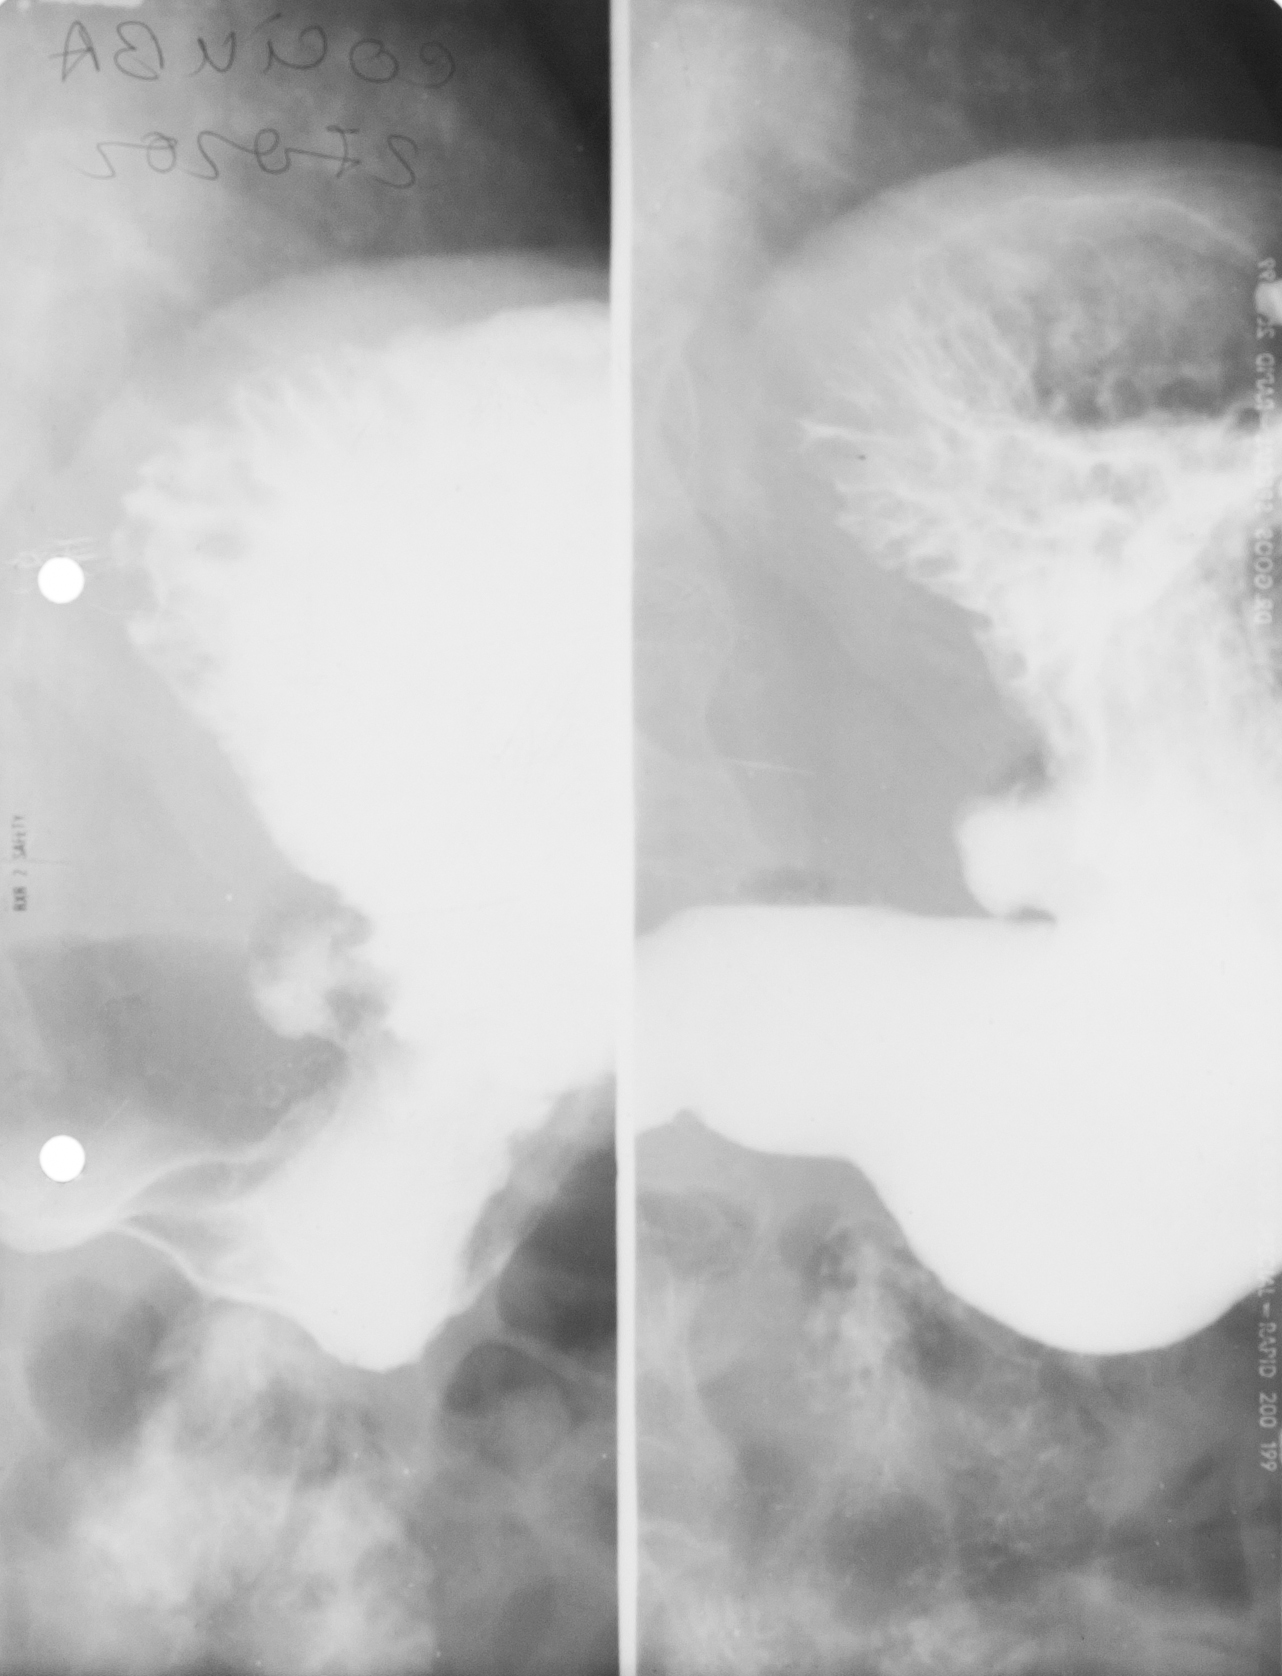

STOMAC NORMOTON(aspectul radiologic)

Tranzitul baritat al stomacului.Aspectul stomacului cu substanță de contrast:forma literei J cu fornix,corp,antru,canal piloric + bulb duodenal,D2(partea descendentă a duodenului

STOMAC ORIENTALIZAT/HIPERTON (aspect radiologic normal)

Stomacul hiperton este caracteristic persoanelor scurte și grase

STOMAC ALUNGIT (aspect radiologic normal)

Stomac alungit cu polul inferior aproape de nivelul crestei iliace.Este caracteristic persoanelor longiline

STOMAC DILATAT

Stomac destins cu substanță de contrast cu polul inferior aflat în micul bazin

Stomac dilatat cu mult lichid de secreție și stază gastrică

: NIȘA BENIGNĂ

Tranzit baritat la nivelul stomacului..La nivelul curburii mici se observă o imagine de adiție mai mult adâncă decât lată,cu pliuri de mucoasă ce converg spre zona respectivă

NIȘĂ BENIGNĂ

Nișă benignă mai mult adâncă decât lată,tot la nivelul micii curburi